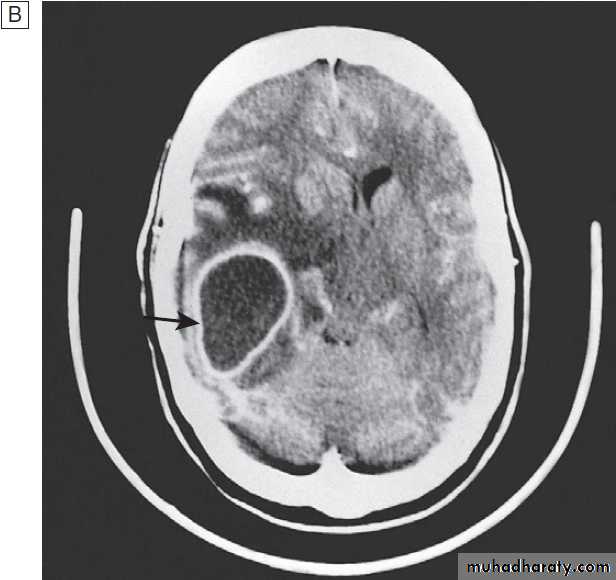

Fig. Different techniques of imaging the head and brain. A Skull X-ray showing lytic skull lesion (eosinophilic granuloma – arrow). B CT

showing complete middle cerebral artery infarct (arrows). C MRI showing widespread areas of high signal in multiple sclerosis (arrows). D SPECT after

caudate infarct showing relative hypoperfusion of overlying right cerebral cortex (arrows).